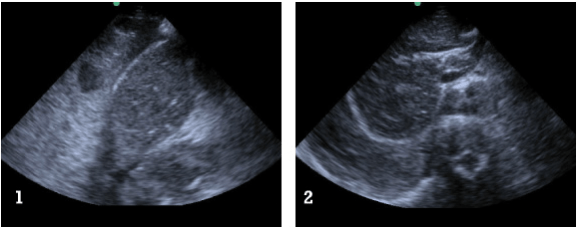

They describe it best: ” ….60-year-old male who collapsed at work and remained unresponsive. They state that there was bystander CPR and a lot of freaking out by coworkers. The only past history they have was from a coworker who thought he had high blood pressure. There was also a witness who told them he was just walking, then doubled over and collapsed without saying a thing. No one knew if he had any symptoms earlier in the day. Paramedics state he was initially in a PEA rhythm at a rate of 120 bpm on the monitor. They started an IV, gave him a 500cc saline bolus, intubated him, and have given three rounds of epi. They estimate a 15 minute down time prior to their arrival and a 10 minute transport time with no return of spontaneous circulation. In fact, things are going in the opposite direction as he has been in asystole for the past five minutes.

They move him onto the bed where your EMT takes over CPR. You note good and symmetric assisted breath sounds via the ET tube, but minimal palpable femoral pulse despite what appears to be good CPR to the tempo of the Bee Gees hit “Staying Alive”. On the monitor there is asystole in two leads. Pupils are fixed and dilated despite no atropine having been received. Things are not looking promising.

You request saline wide open and a final round of epinephrine while you take a look for cardiac motion with the ultrasound machine. To minimize interruption of CPR you don’t have the EMT pause until you are completely ready to look. You also have the RT hold respirations to avoid any artifact. There is no cardiac motion. You verbalize this to your team. The heart does not appear dilated and there is no pericardial effusion. You ask aloud, “anyone have any other suggestions” prior to calling the time of death.

Of course you next wonder what did him in: MI, PE, something else… His belly looks pretty protuberant, so you decide to take a quick look at his abdomen to check for free fluid. What you see is shown in the two images below. ”

Screen Shot 2013-08-27 at 6.26.16 PM

What do you think killed this gentleman? Trust me, you want to read more and see what exactly the ultrasound image is  – as it is quite an interesting finding: go here.